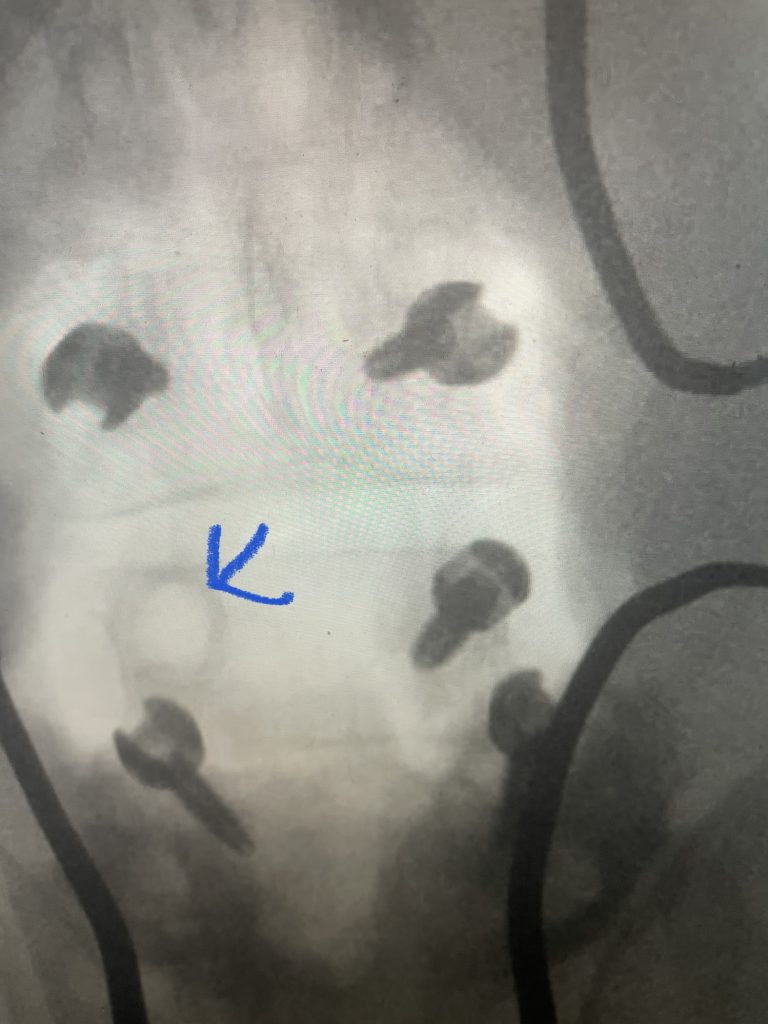

Other maneuvers are always having a ready feeling of letting go of the tissue, having a light touch like “pumping your brakes”. Also, it is sometimes necessary to “shovel” the tissue, not bite it, with the Kerrison (Fig 2), utilizing the device as a dissecting instrument as well. It is also important to be patient and take the tissue in two bites, if necessary. It is ok to bite thickened tissue incompletely with the Kerrison if one is not sure if the consequence would be a leak or tear in the membrane if adhesions are present; dissect the adhesion with a Penfield 4 and cut it with a Metzenbaum scissors and then proceed with the finishing bite. The older patients are particularly challenging given the quality of their dura; it is often quite thin and floppy. A useful technique is employing an ultrasonic device (Fig 3) to remove enough of a shelf of bone to gain a dissection plane to allow for Kerrison to take over. And one can start with a 1 or 2 mm Kerrison to make a start under the edge of the bone and compressive soft tissue and advance to a 3 or 4mm.

Fig 3: Demonstrating the Misonix ultrasonic emulsifier to safely remove bone without injuring the dura and soft tissues.